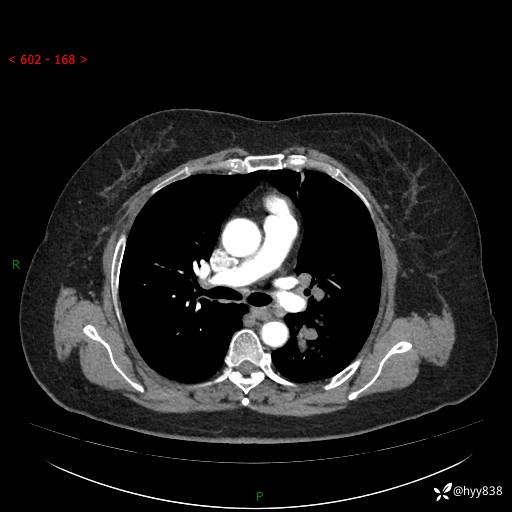

老年女性,左上肺结节8年。典型又不典型,看你如何解读---结果公布(值得分析)

主诉:检查发现左上肺结节8年,较前增大。

简要病史:患者于8年前体检行胸部CT检查发现左上肺结节(4mm),患者平素间断咳嗽咳痰,无心慌、胸闷、胸痛、呼吸困难、低热、盗汗,无头痛、头晕,无腹痛、腹胀等不适,未行特殊处理,定期复查。2023-09-21胸部CT示左上肺结节(2cm)较前增大,2024-02-01胸部CT示左上肺尖后段(39*32mm),左侧肺门及纵隔淋巴结增大,现患者欲求手术治疗,遂来我院就诊,以“左上肺结节”收入我科。 患者自起病以来,精神可,睡眠可,饮食可,大小便正常,体重无明显改变。

辅助检查:CT

胸部CT平扫

增强(动脉期+静脉期)